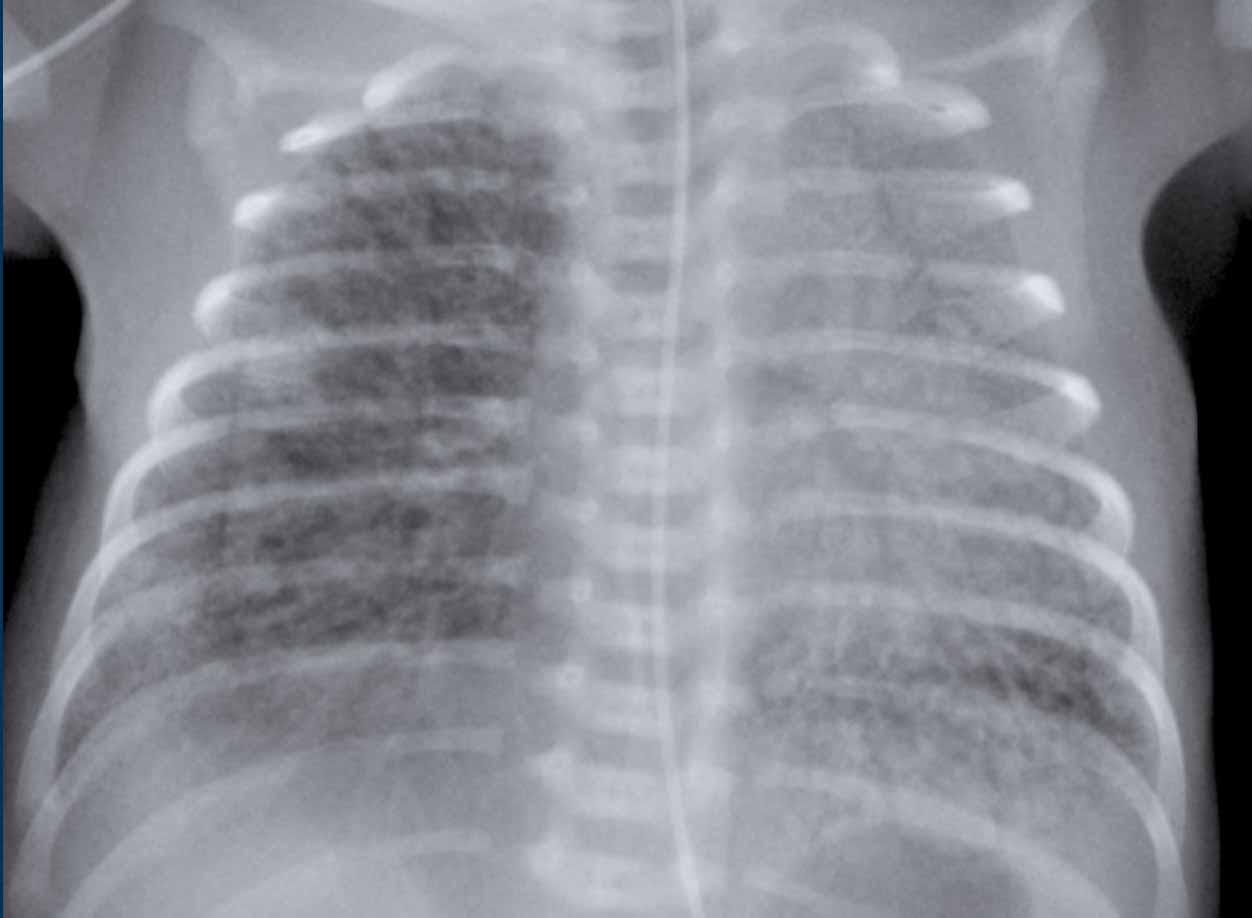

One week old neonate, born at 27 weeks of gestational age.

Image

- Vị trí ống nội khí quản quá sâu, cần được điều chỉnh lại về giữa khí quản.

- Diffuse granular opacification of both lungs.

- Air bronchograms.

- Các mạch máu phổi không còn nhận ra được nữa, nhưng bóng tim vẫn còn có thể nhận ra được.

- Opacification of the left lower lobe caused by atelectasis.

Không phân loại vì trẻ sơ sinh này đang được thở máy.